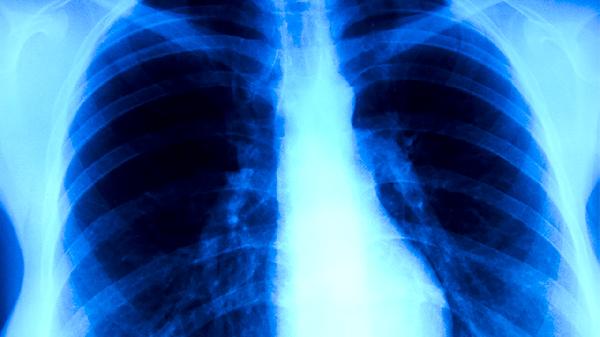

紫龙金片是一种中成药制剂,主要成分包括黄芪、当归、白英、龙葵等中药材,具有益气养血、清热解毒的功效。在肺癌治疗中,紫龙金片常作为辅助用药,配合手术、放疗或化疗使用。该药可帮助改善患者免疫功能,减轻放化疗引起的恶心呕吐、乏力等不良反应,提高患者生活质量。临床观察显示,部分患者用药后食欲改善,体力有所恢复。

需要注意的是,紫龙金片不能替代肺癌的主要治疗手段。中晚期肺癌患者仍需以手术、靶向治疗或免疫治疗等规范治疗为主。个别患者可能出现轻度胃肠道不适,过敏体质者慎用。用药期间应定期复查血常规和肝肾功能,避免与其他中药同时服用可能产生的药物相互作用。

肺癌患者在遵医嘱使用紫龙金片的同时,应注意保持均衡饮食,适当补充优质蛋白和维生素,可选择鱼肉、鸡蛋、西蓝花等食物。根据体力状况进行适度活动,如散步、太极拳等。保持居住环境空气流通,避免呼吸道感染。定期复查胸部CT等检查,监测病情变化。出现咳嗽加重、咯血等症状应及时就医。